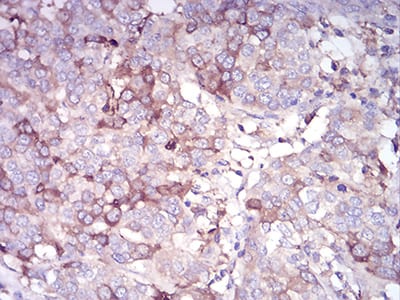

Immunohistochemical analysis of paraffin-embedded human bladder cancer tissues using CDH11 mouse mAb with DAB staining.